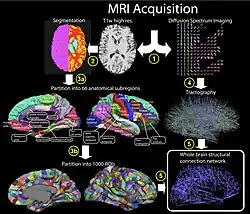

Коннекто́м (англ. connectome /kəˈnɛktoʊm/) — полное описание структуры связей в нервной системе организма[2][3]. Область исследований, включающая в себя картографирование и анализ архитектуры нейрональных связей, называется «коннектомика». Некоторые исследователи называют коннектомом карту связей не всего организма, а его части.

В 2005 доктор Олаф Спорнс из университета Индианы и доктор Патрик Хагман из госпиталя Лозаннского университета независимо и одновременно предложили термин «коннектом» для обозначения карты нейронных соединений в мозге. Это название было предложено из-за созвучия с термином «геном».

«Коннектомика» (Хагман, 2005) была определена как наука о сборе и анализе данных коннектома.

В 2005 году доктор Хагман в своей статье «От диффузионной МРТ головного мозга к коннектомике» писал:

Пути через мозговое белое вещество могут быть определены с помощью гистологического исследования методом дегенерации и аксональной трассировки. Метод аксональной трассировки — первичный базис картирования длинных мозговых путей белого вещества в обширную матрицу соединений между регионами серого вещества. Первые подобные исследования проводились в зрительной коре макаки (Феллман и Ван Эссен, 1991) и таламо-корковом пути в кошачьем мозге (Сканнел и др., 1999). Создание баз данных для подобных массивов анатомических соединений позволяет постоянно их обновлять и увеличивать их точность. Яркий пример подобных баз данных — онлайн-база данных соединения кортекса макак CoCoMac (Кётер, 2004).

Сети соединений мозга могут быть представлены в разных масштабах, что соответствует уровням пространственного разрешения в визуализции головного мозга (Кётер, 2007; Спорнс, 2010). Эти уровни могут быть грубо классифицированы как микромасштаб, мезомасштаб и макроуровень. В конечном счёте можно будет присоединить результаты, полученные на разных уровнях, в единую иерархическую карту нейрональной организации, которая сможет показать отдельный нейрон в популяции нейронов до таких больших систем, как кортикальные области. Из-за того, что у разных индивидов будут отличия в коннектомах, любая унифицированная карта скорее всего будет предоставлять вероятностную информацию о связности нейронов (Спорнс и др., 2005).

Коннектом на макроуровне (с разрешением в миллиметры) пытается захватить большие мозговые системы. Базы данных коннектома на микроуровне и мезоуровне могут быть значительно более компактными, чем на клеточном уровне.